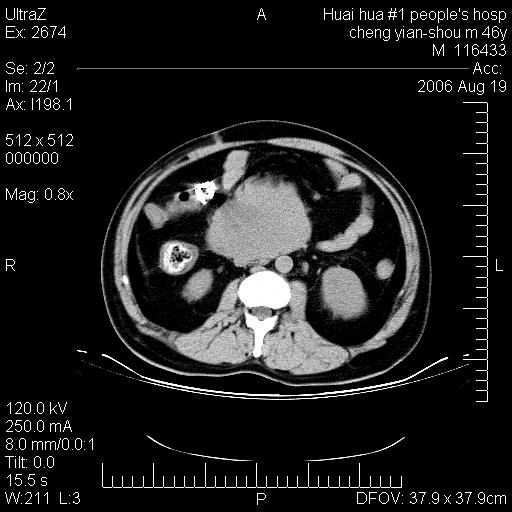

患者,男,46y。腹痛2月,消瘦。

十二指肠水平段占位,考虑间质瘤或平滑肌瘤。

肿块较大,腹膜后占位,境界欠清,周边脂肪密度较高呈条状影,有没有脂肪肉瘤可能,

缺少完整的三期图像。考虑肠系膜脂膜炎mp(肿块型)。

十二指肠水平段占位,考虑间质瘤。

首先考虑小肠间质瘤。

十二指肠水平段软组织密度占位,考虑间质瘤可能性大。

腹膜后占位,境界欠清,考虑来源于十二指肠病变,间质瘤或平滑肌肉瘤可能性大。建议活检。

手术病理结果:原发性小肠恶性淋巴瘤(primary gastrointestinal lymphoma,pgil)是原发于胃肠的淋巴网织系统的恶性肿瘤,在结外淋巴瘤中居第一位,该病少见,临床无特异性,诊断困难,术前主要依靠影像学诊断。胃肠道本身具有较丰富的淋巴组织,因而胃肠原发性淋巴瘤是结外淋巴瘤最常见的部位,文献报道约占胃肠道恶性肿瘤的1%~4%,其中胃约占50%~70%,小肠约占35%~70%,结肠约占4%~6%。影像检查在pgil的诊断及分期中有重要的作用,ct是很有价值的检查方法。

胃肠淋巴瘤病理特点:胃肠道原发性淋巴瘤起源于胃肠壁固有层和黏膜下层的淋巴组织即胃肠粘膜相关淋巴组织(malt),多为粘膜相关淋巴瘤。病理上通常为非霍奇金淋巴瘤,且决大多数来源于b淋巴细胞,很少见于霍奇金淋巴瘤。胃肠原发淋巴瘤比胃肠道癌的发病率要低的多,最常见于胃,其病因可能跟幽门螺杆菌感染有关。幽门螺杆菌能引起胃粘膜损害,引起炎性及免疫反应,淋巴细胞聚集并形成滤泡,可影响胃的正常生理功能,导致胃淋巴瘤的发生。单纯性小肠淋巴瘤是常见好发于回盲末端,受累的肠段较长,可单发、多发,甚至累及整个小肠。原发性大肠淋巴瘤罕见,以直肠和盲肠最多见。病变大体观可表现为胃肠腔内外的肿块,也可表现为从黏膜下到浆膜面肠壁的纵向浸润,并且常常伴有肠系膜淋巴结肿大。任何情况下,肿瘤几乎总是导致一定程度的肠壁增厚,可对称或不对称,病变与正常组织间常无明确分界,肠腔可狭窄、正常或动脉瘤样扩张,后者主要是肿瘤在肠壁内浸润,破坏肠壁内植物神经丛所致。以上改变成为ct检测病变的病理基础。

肠道淋巴瘤的ct表现分为4类

1) 壁内浸润型, (2)多发结节型, (3)肠系膜受累伴腔外肿块型(本型就是),(4)肿块型。